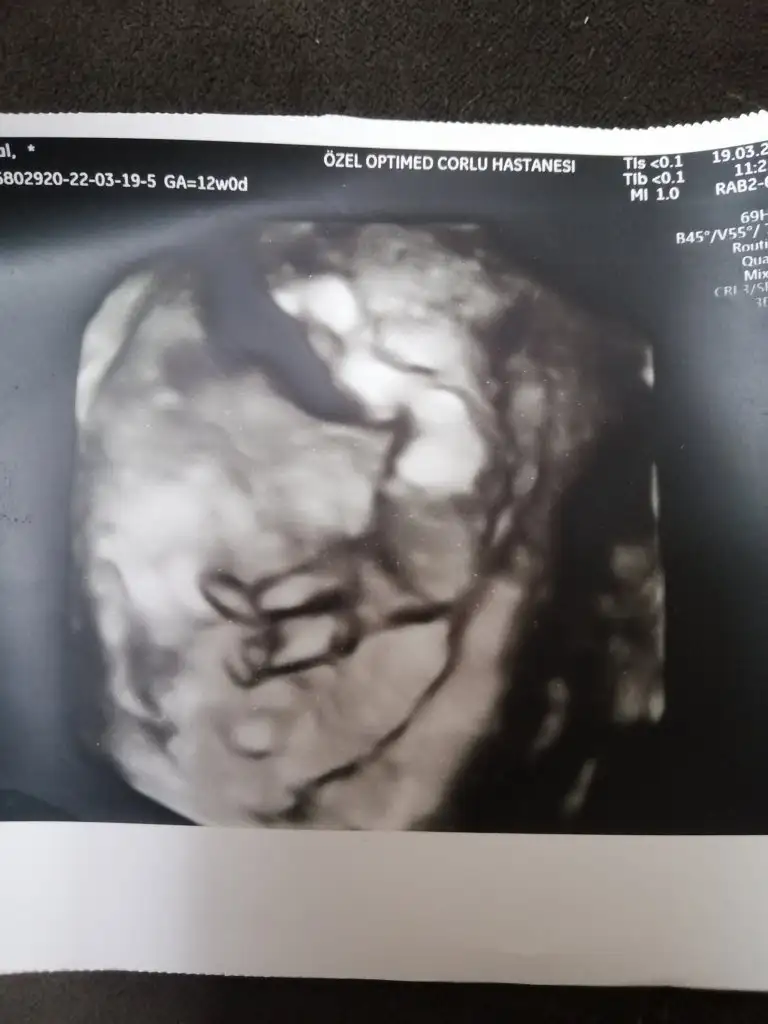

Merhaba.banada söyler misiniz 🤗biri 8 hafta diğeri 12 🌼